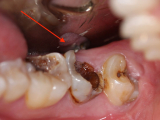

RĂNG SÂU NẶNG CÓ BỌC SỨ ĐƯỢC KHÔNG ?

Sâu răng là bệnh lý răng miệng phổ biến, không chỉ gây đau đớn, ảnh hưởng đến chức năng ăn, nhai mà sâu răng còn gây mất thẩm mỹ cho người bệnh.